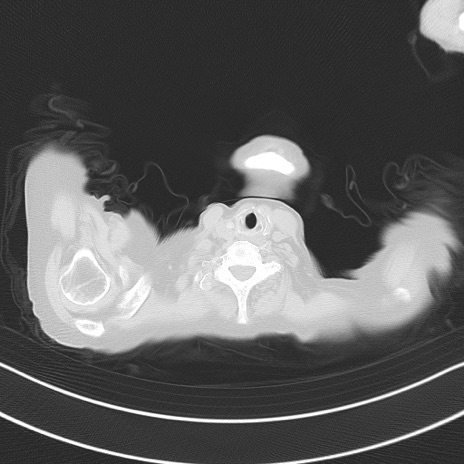

症例40(横断像)他院1日前

横断像

他院CT